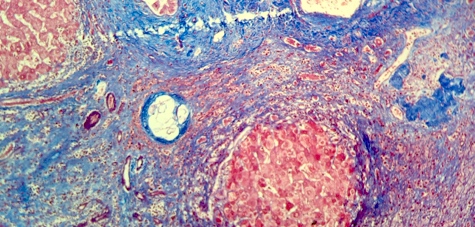

Microscopic (histologic) description

- Ova are mainly seen in the loose submucosa of large intestine, usually with formation of granulomas and infiltration by eosinophils and inflammatory cells

- Later the muscularis mucosa becomes involved and the overlying mucosa shows small superficial ulcers

- Fibrosis develops in chronic stage, when only calcified eggs are seen

Microscopic (histologic) images

Contributed by Nalini Bansal Gupta, M.D., Lisa Cerilli, M.D. and @zaalruwai83 on Twitter